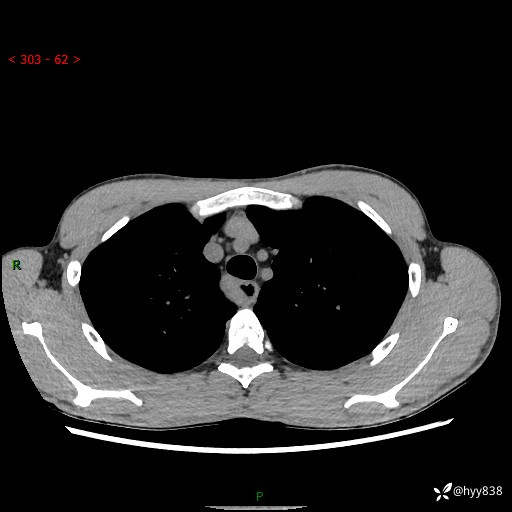

年轻男性,发现后纵隔占位1周余。征象简单,难在定位---结果公布~

现病史:患者于1周前体检行检查发现后纵隔占位,患者平素无明显咳嗽咳痰,无心慌、胸闷、胸痛、呼吸困难、低热、盗汗,无头痛、头晕,无腹痛、腹胀等不适。现患者欲求进一步治疗,遂来我院就诊,以“纵隔占位”收入我科。 患者自起病以来,精神可,睡眠可,饮食可,大小便正常,体重无明显改变。

胸部CT平扫+增强